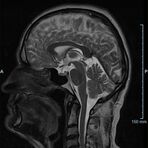

Kopf/Hals

Kopf

• akute Schlaganfalldiagnostik und chronische Durchblutungsstörungen

• entzündliche Prozesse des Gehirns oder der Gesichtsweichteile

• Tumore, ggf. mit Spektroskopie

• Abklärung Schwindel, zentrale Sehstörung, Kopfschmerz

• Metastasenverdacht

• Multiple Sklerose

• Abklärung Hirnnerven, Schädelbasis inkl. Hypophyse

• Abklärung Kleinhirn, Hirnstamm, Halsmark